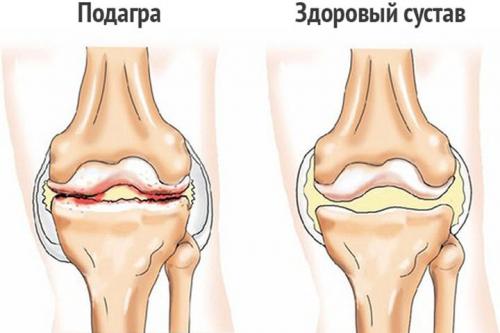

- подагра. В результате расстройства регуляции метаболизма пуринов в суставах начинают откладываться кристаллы солей мочевой кислоты. Постепенно они укрупняются, образуя ураты. Эти мелкие конкременты раздражают суставные структуры, провоцируя постоянное ощущение жжения. Во время подагрических атак оно сменяется острой, пронизывающей болью;